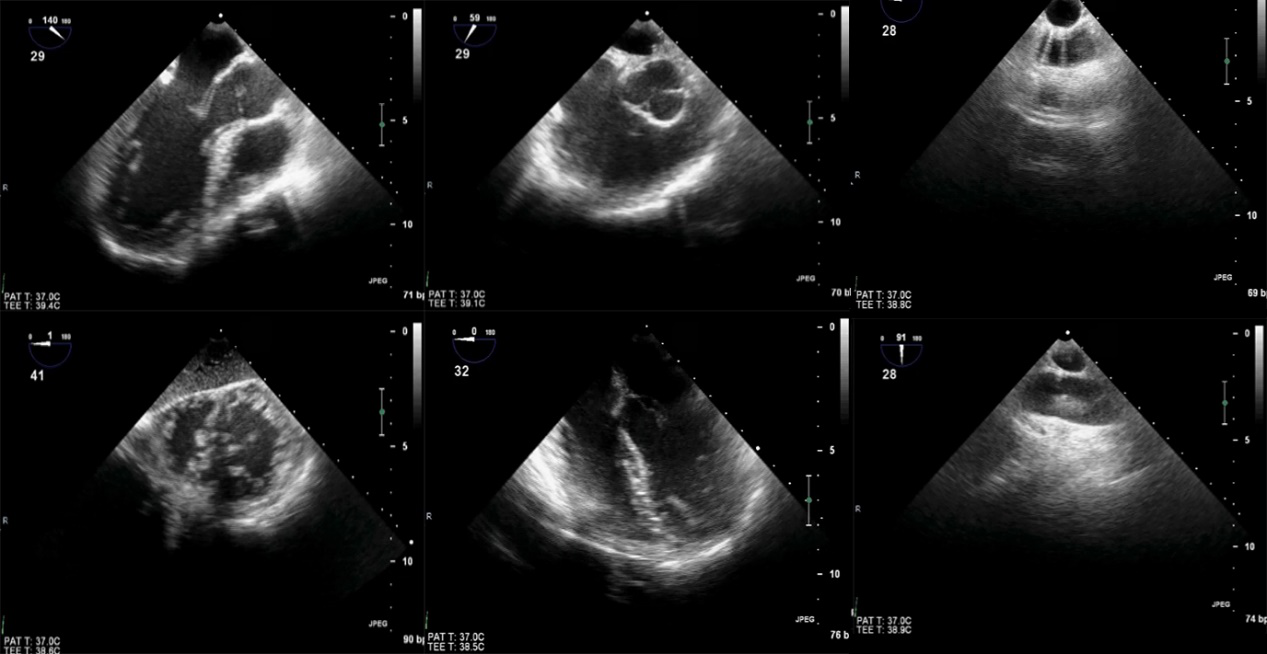

图5 Focus-TEE 6个基本切面的2D图像

图6Tee-Focus中的6个基本切面的模型切面

截至目前,TEE-FOCUS包涵6个基本切面(图5,6),其中有4个关于心脏的基本切面和2个关于大血管的基本切面:①左心室长轴切面,②右心室流入流出道切面,③经胃底心室短轴切面,④食管中段四腔心切面,⑤降主动脉短轴切面,⑥升主动脉长轴切面(新增)。